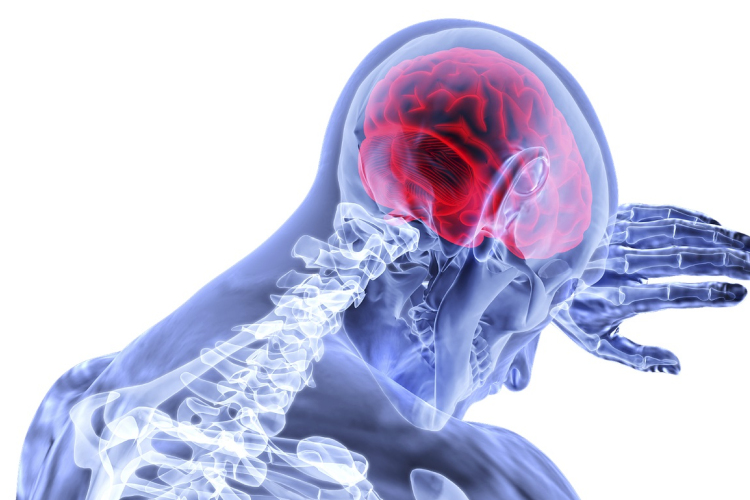

Új idegsejttípusokat azonosító kutatási program zárult le Szegeden

Az emberben és más fajokban ezidáig ismeretlen idegsejttípusokat azonosító kutatási program zárult le Tamás Gábor professzor vezetésével a Szegedi Tudományegyetemen